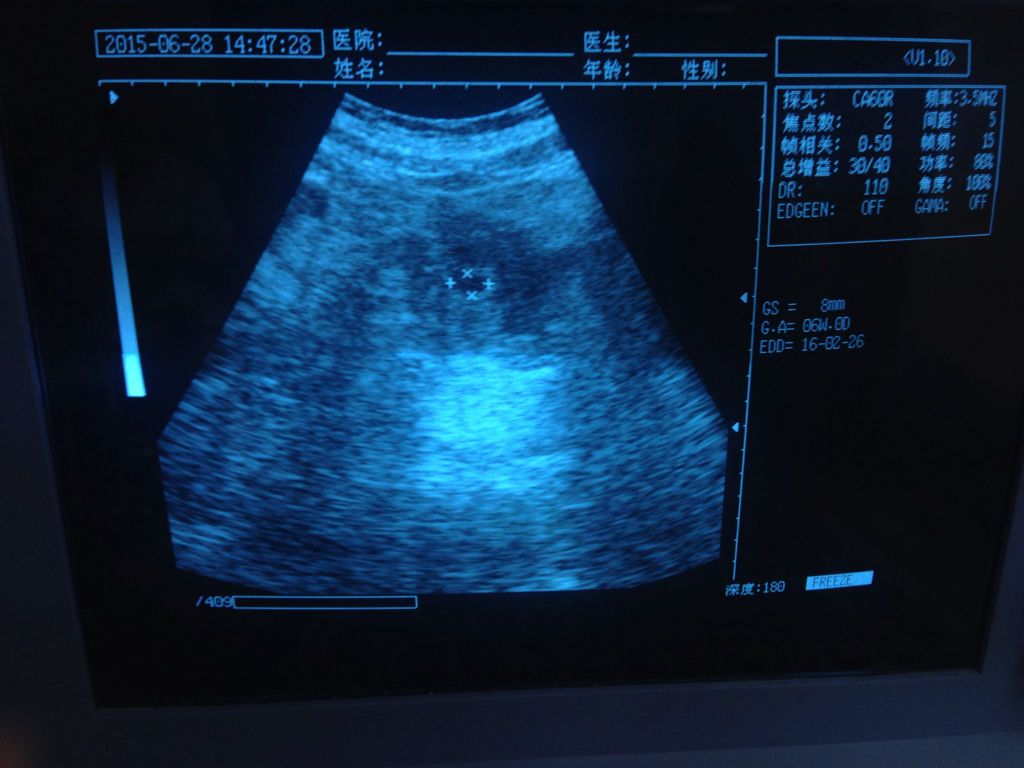

您好。根据您的B超检查孕囊大小8毫米。提示怀孕基则哑侨寸大约38天左右。孕囊内没有看见胎芽胎心。如果倘筝仅根据今天一次的B超检查,还不能确定胚胎发育是否正常。需要再进一步观察。建议卧床休息,禁止性生活。7天以后再次复查B超。